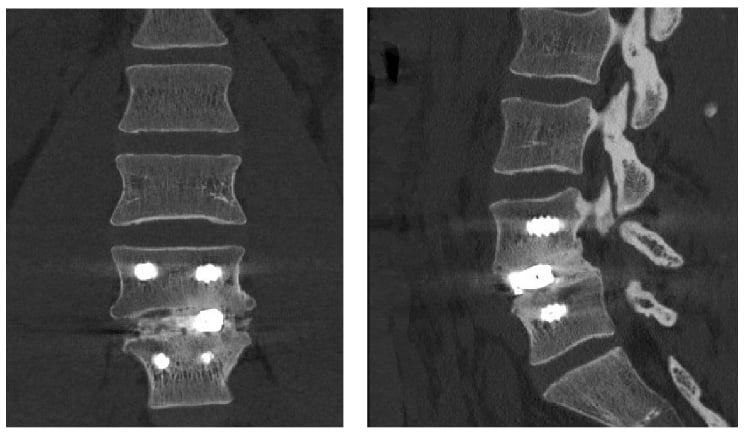

Postoperatively, the patient’s axial back pain and radicular symptoms resolved. At 1-year follow up he was pain free, and computed tomography (CT) scanning demonstrated successful interbody fusion.

Figure 4: 1-year postoperative CT scan demonstrating successful interbody fusion at L4–L5.